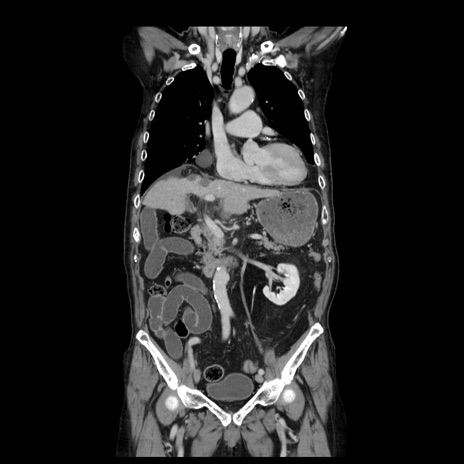

症例21(冠状断像)

【症例】70歳代男性

【主訴】腹痛

【現病歴】肝硬変・肝細胞癌にてかかりつけの方。約9時間前に食後より腹痛出現。症状が徐々に増悪し、嘔吐出現したため来院。

【既往歴】肝硬変、肝細胞癌(RFA、TACE後)

【身体所見】意識清明、表情苦悶様、BT 36℃、BP 129/78mmHg、P 88bpm、SpO2 97%(RA)、右上腹部から心窩部にかけて圧痛あり、反跳痛なし、筋性防御あり。

【データ】WBC 5800、CRP 0.16